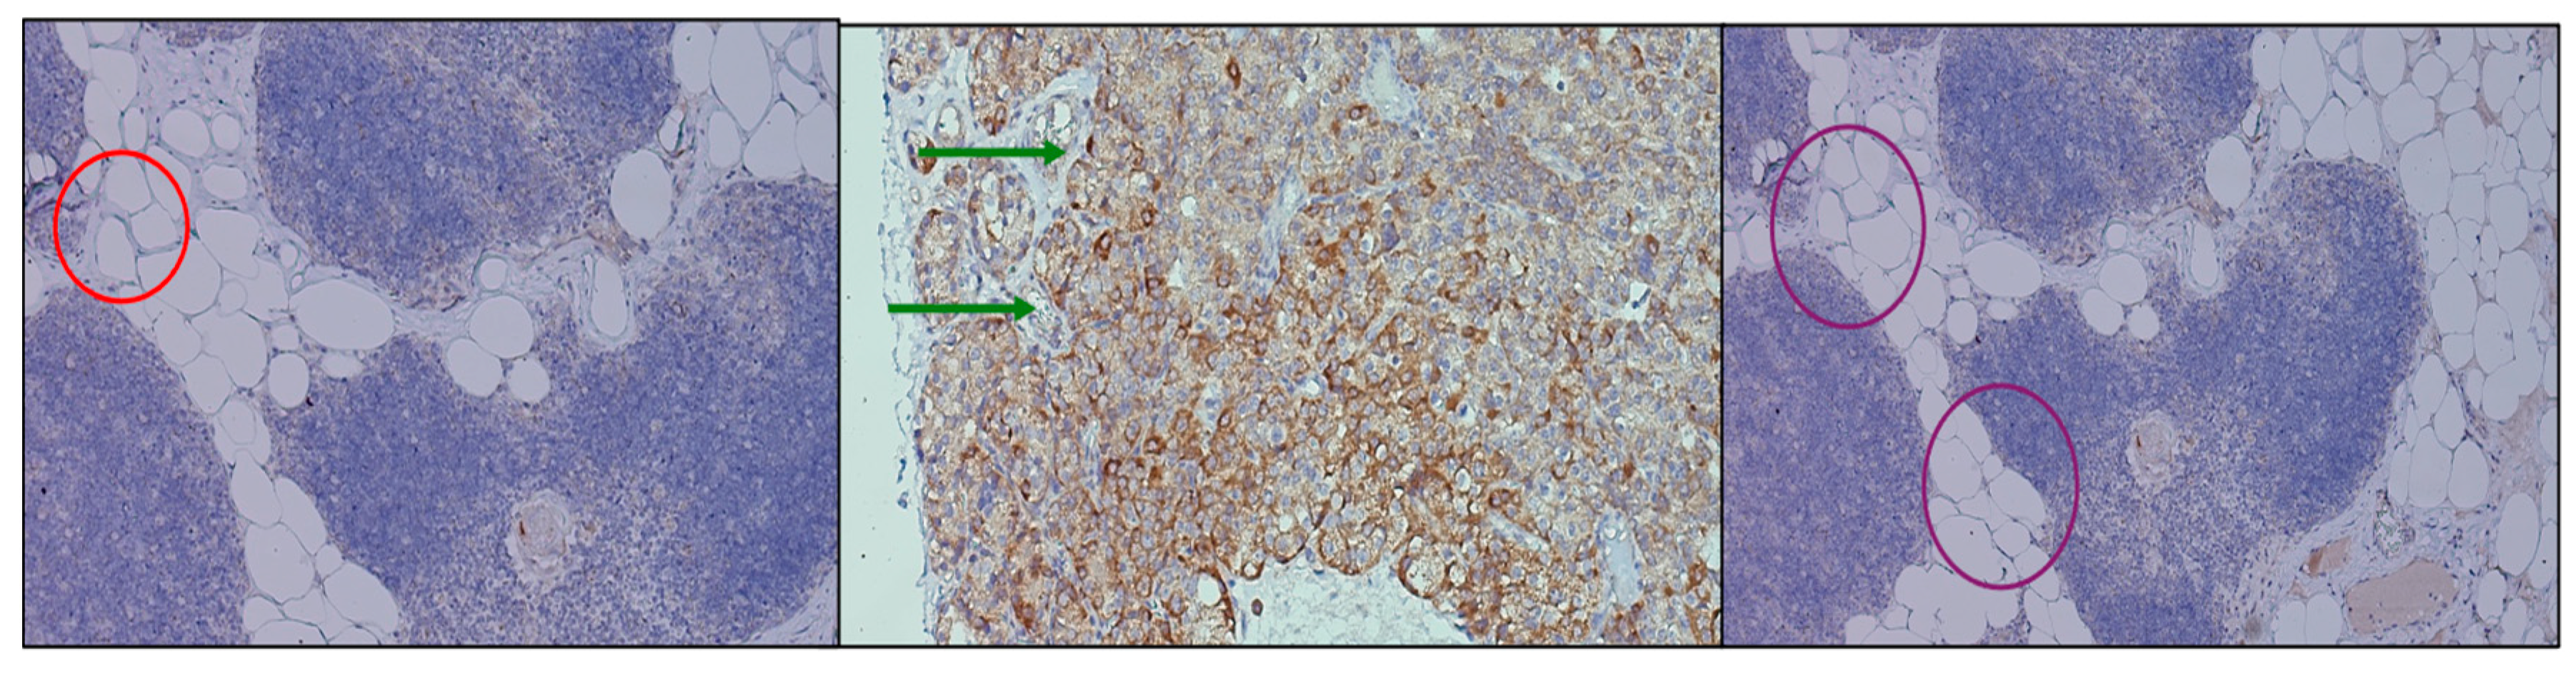

Immunohistochemical assessment of PTH1R expression revealed distinct yet convergent patterns across the investigated tissues. In the thymic samples, receptor positivity was faint and diffuse, predominantly localized within the stromal framework, suggesting a basal but not absent signaling role. In contrast, parathyroid adenomas exhibited strong, polarized staining, with an apical distribution in clusters of chief cells, indicating an active involvement of PTH1R in pathological glandular proliferation and secretory modulation. Parathyroid tissue excised during thyroidectomy showed a more heterogeneous profile, with groups of chief cells displaying variable levels of receptor expression, ranging from moderate to weak intensity. This heterogeneity (Figure 3) may reflect the functional diversity of non-adenomatous parathyroid glands. These findings confirm the presence of PTH1R in both thymus and parathyroid tissue, with different intensities and topographic localization, reinforcing the hypothesis of a parathyroid–thymus molecular axis while also highlighting organ-specific adaptations of receptor distribution.

Figure 2. Parathyroid tissue with Thymosin staining at 40×. (Left) adenomatous parathyroid with apical staining indicated by green arrows. (Right) parathyroid associated with thyroidectomy, showing variable expression in chief cells outlined in purple. These patterns emphasize polarized and heterogeneous expression, in contrast to the diffuse thymic distribution.

Figure 3. Comparative immunohistochemical staining for PTH1R across thymus and parathyroid tissue at 40×. (Left) Thymus (red circle), where staining is weak and diffuse, consistent with low receptor density. (Center) Parathyroid adenoma (green arrows), showing strong, predominantly apical membrane staining in clusters of chief cells. (Right) Parathyroid tissue excised during thyroidectomy (purple circles), with heterogeneous and moderate expression in groups of chief cells. The presence of PTH1R in both glands, albeit at different intensities and topographies, supports the hypothesis of a functional parathyroid–thymus molecular axis.